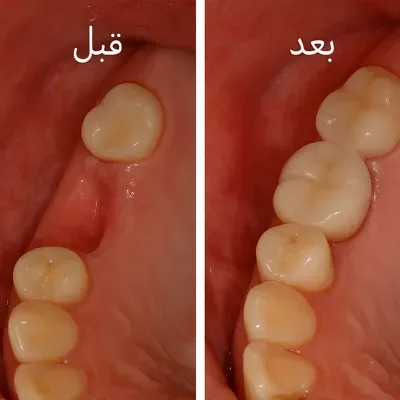

قبل و بعد کاشت دندان طبیعی با روکش سفید